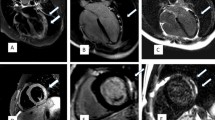

Vaccine-associated pericarditis. 57-year-old male admitted to ED for chest pain, fatigue and dyspnea after 8 days following second dose of Comirnaty vaccine. The first CMR (a–f), performed for the clinical suspicion of myocarditis, showed edematous thickening and enhancement of pericardial layers (red arrows) respectively on STIR T2-weighted (a) and fat-suppressed turbo spin echo T1-weighted (b) images. Absence of myocardial injury and pericardial enhancement (arrowheads) has been detected on late gadolinium enhanced images acquired on short axis (c) and horizontal long axis (d) view. Myocardial native T1 (e) and T2 (f) values were within normal range on corresponding maps. At 13-weeks follow-up CMR, there were neither pericardial fluid nor edema on STIR images (g) nor myocardial LGE areas (h)